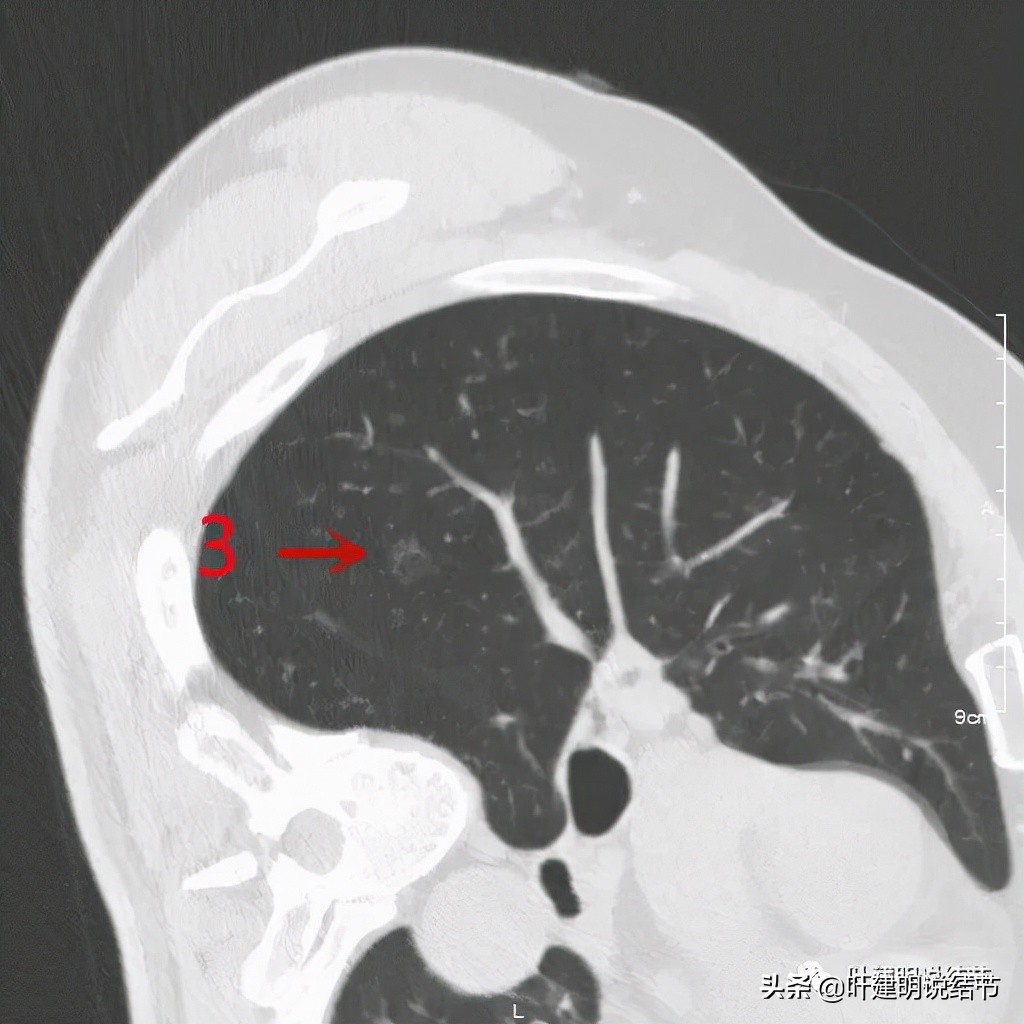

右侧病灶3:淡磨玻璃结节,边缘略模糊,考虑不典型增生或肺泡上皮增生可能性较大些